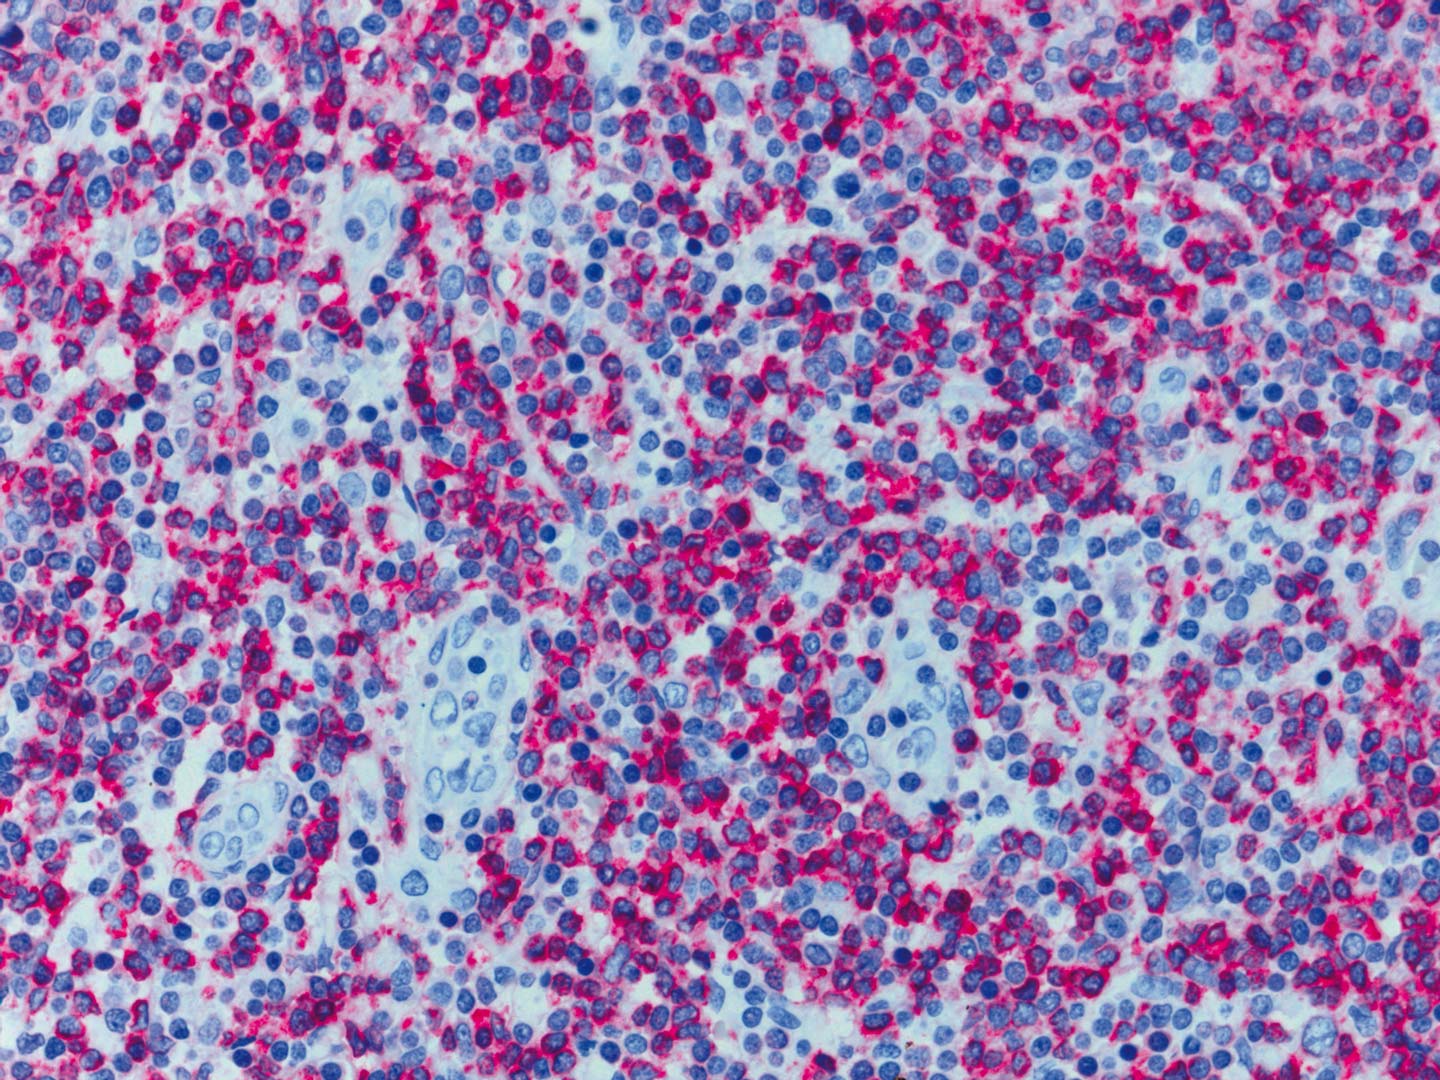

組織學標本(人)

組織學標本(人) 染色體標本(人)